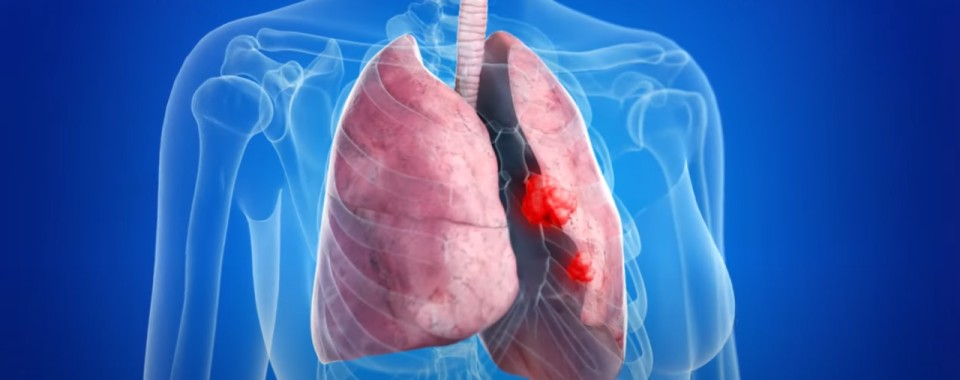

폐렴 증상 폐렴은 폐의 세균, 바이러스, 곰팡이 등 감염으로 인해

폐포(폐 속의 공기 주머니)에 염증이 생기고, 고름이나 액체가 차는 질환입니다.